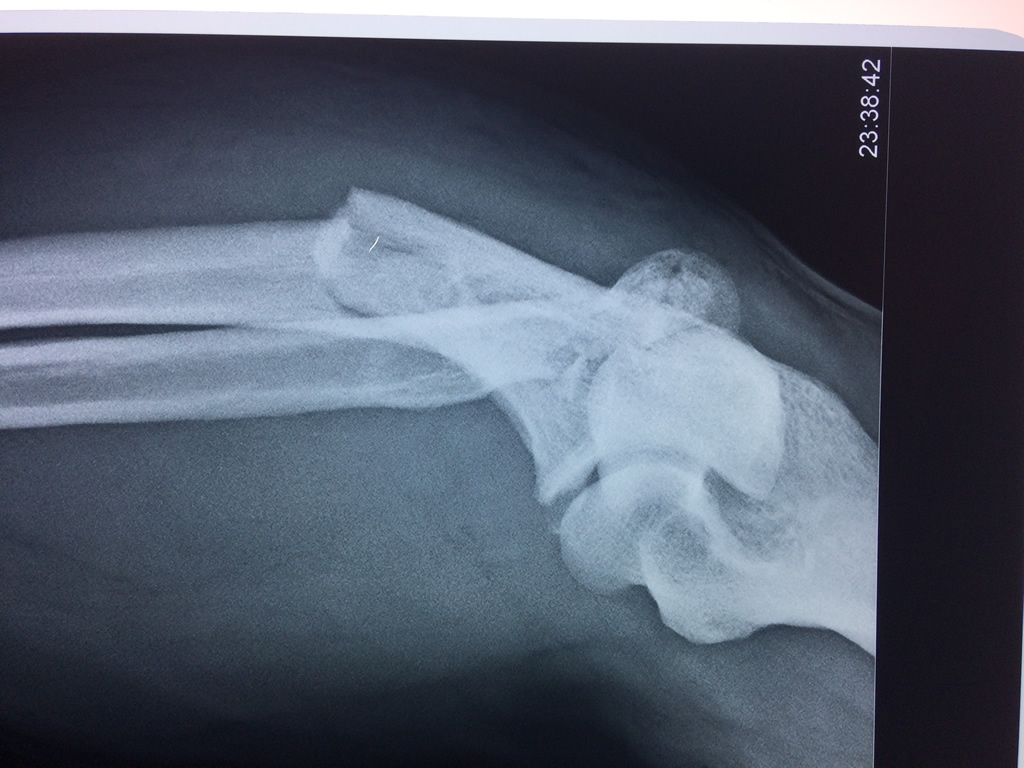

Cirugias en El Salvador - Codo